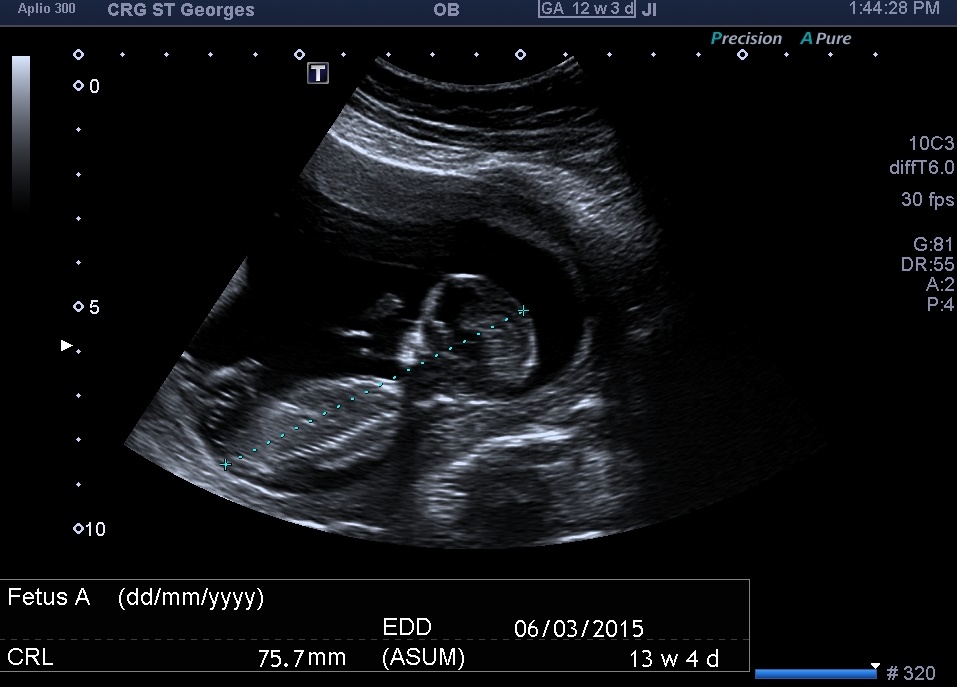

Attachment 20622Attachment 20621 Attachment 20623 Attachment 20624

I hope you can make a guess, i have to wait another 6-7 wks to find out the gender and i just like to hear your guesses

Can I ask what makes you say boy? Cos i cant see it haha!

I'm gonna say boy too.the nub in your last pic is very boyish x